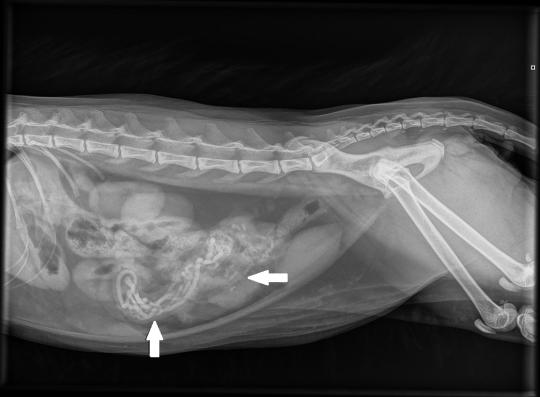

Die Vorgeschichte lässt natürlich aufhorchen, entsprechend werden umgehend Röntgenaufnahmen des Bauches angefertigt. Hier sind diverse längliche, röntgendichte Fremdkörper zu sehen - bei einigen ist unklar, ob sie nicht schon im Dickdarm angelangt und damit problemlos sind; bei anderen besteht insbesondere auf der Aufnahme in Rückenlage der Verdacht, dass sie im Dünndarm stecken und sich dieser über dem Fremdkörper aufgefältelt hat. Das Katerchen muss aufgrund des Darmverschlusses schnellstmöglich operiert werden.